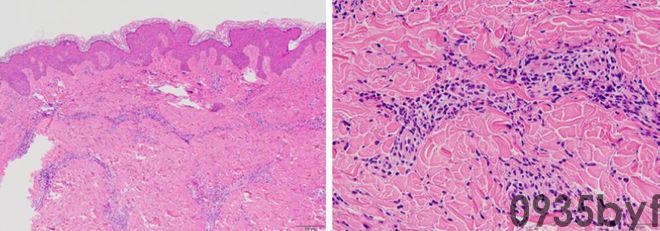

患者男,14岁,反复红斑10年,累及面部、躯干和四肢,并伴有足跟疼痛。值得注意的是,在就诊前5年,患者体重明显增加,且反复发烧。其母亲和祖母有类似的反复红斑及听力障碍,祖母患肥胖症和糖尿病。

体格检查:躯干和四肢有风团样红斑、丘疹。体重71.3kg,身高160.5cm,体质指数为27.6kg/m2。